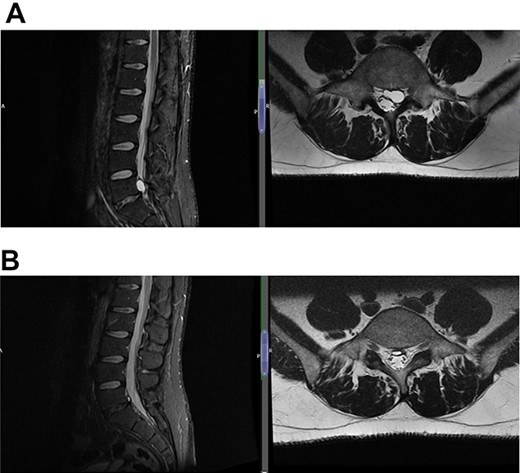

(A) Case 4—an initial MRI showing multilevel degenerative disc disease and a cyst at the lumbar L5/S1 which is causing impingement on the left S1 nerve root, and (B) case 4—comparison was made with the previous MRI; post-contrast scan shows that the L5-S1 left-sided cystic features have nearly diminished; no neoplastic lesion is detectable.